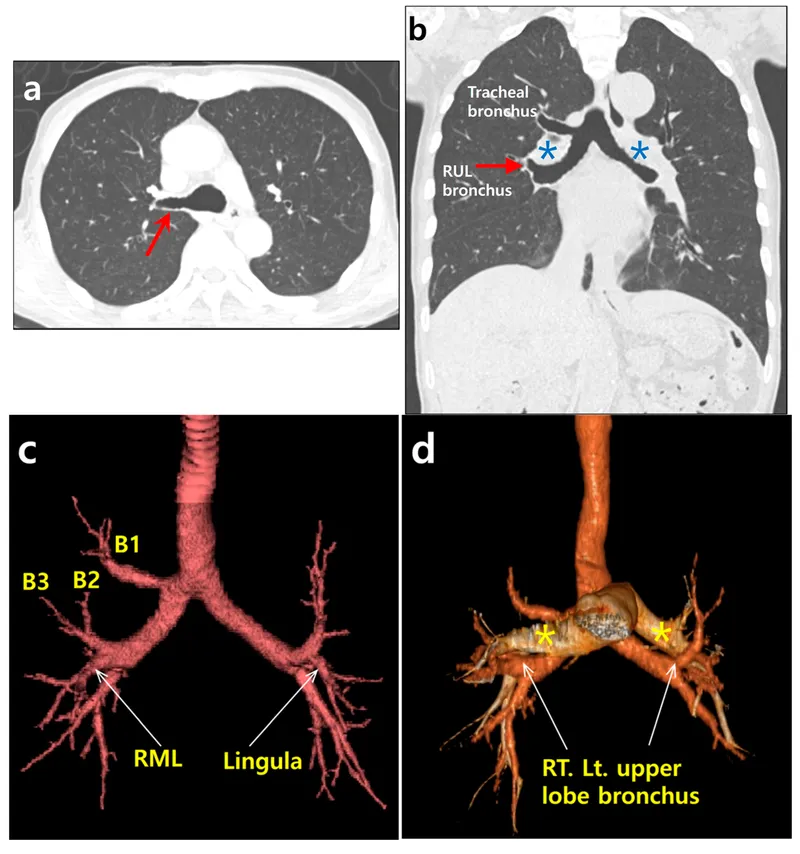

CT Thorax: Lungs & Pleura - Lung Lobes Logic

- Lobar Anatomy:

- Right: 3 lobes (RUL, RML, RLL).

- Left: 2 lobes (LUL, LLL); Lingula (LUL) like RML.

- Fissures:

- Major (Oblique): Bilateral; separate lower from upper/middle lobes.

- Minor (Horizontal): Right only; separates RUL from RML. Often incomplete.

- Segmental Anatomy (Simplified) 📌

- RUL: Apical, Posterior, Anterior (APA)

- RML: Lateral, Medial (LM)

- RLL: Superior, Anterior basal, Medial basal, Lateral basal, Posterior basal (SAML P)

- LUL: Apico-posterior, Anterior; Lingula: Superior, Inferior (APASI)

- LLL: Superior, Anteromedial basal, Lateral basal, Posterior basal (SALP)

- Bronchovascular Bundles:

- Artery & bronchus central per segment (bundle).

- Veins intersegmental, peripheral.

⭐ Right minor fissure often incomplete/absent (~20-50%); complicates RML pathology diagnosis (e.g., atelectasis).